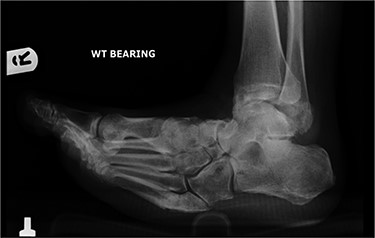

A 62-year-old male with a 22-year history of insulin-dependent diabetes and associated neuropathy and retinopathy presented following a fall. He sustained a fifth metatarsal base fracture of his right foot with resultant de-functioning of the peroneus brevis. This led to progressive varus of the forefoot, with subsequent midfoot collapse as a result of Charcot neuroarthropathy (Figs 1 and 2).

Anterior–posterior radiograph of right foot demonstrating fracture at base of fifth metatarsal and forefoot varus.